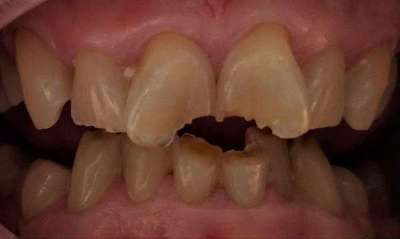

Crowns placed on front teeth to fix worn edges and darkening color of teeth. Crowns created harmony amongst the front teeth and gave the patient a more youthful smile.